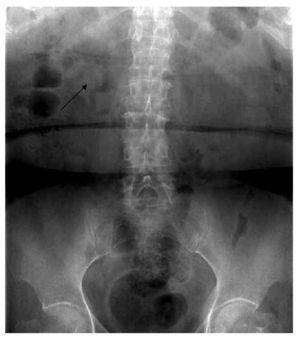

Se ingresó por hematuria macroscópica, anemizante, formadora de coágulos amorfos y dolor cólico nefrítico bilateral, náuseas y vómitos, además de una respuesta inflamatoria sistémica manifestada por mal estado general, cuadros de hipertermia e hiporexia. En los exámenes de laboratorio tenía leucocitos totales de 12 400, hemoglobina 10.3 g/dL, hematocrito 31.1, plaquetas 441 000, glucosa 140 mg, urea 117.1 mg/ dL, nitrógeno ureico 55.0 mg/dL, creatinina 3.0 mg/dL, cloro 106 mmol/L, potasio 4.5 mmol/L, sodio 130 mmol/L, urocultivo positivo a Escherichia coli. En imágenes, desde la placa simple de tracto urinario se observaba la presencia de gas en topografía ureteral, siendo más evidente en el tercio superior de uréter derecho. En la tomografía se observaron signos de pielonefritis enfisematosa bilateral, caracterizada por colección de gas en cavidades renales izquierdas y en el parénquima renal del polo superior derecho, así como en uréter de manera bilateral, con ureteropielocaliectasia bilateral sin presencia de imágenes hiperdensas relacionadas a litos. En cortes coronales, se observó la ureteropielocaliectasia en la zona por donde se cruza el uréter con la vena ovárica de manera bilateral.

El caso que presentamos es una paciente con infección de vías urinarias complicada en pielonefritis enfisematosa bilateral, secundaria a uropatía obstructiva por la vena ovárica bilateral, por lo anterior tiene la particularidad de estar en el 11% de la presentación general, ya que dentro de los estudios de imagen no se evidenció la presencia de otro proceso obstructivo que condicionara la ureteropielocaliectasia y por consiguiente, el proceso enfisematoso. El cuadro clínico fue muy inespecífico, y la paciente fue ingresada por complicación de una pielonefritis enfisematosa. En la Figura 1, se observa un proceso enfisematoso en el uréter en el tercio proximal derecho. En la Figura 2, se observa ectasia bilateral con gas en parénquima renal en el polo superior derecho y en las cavidades del riñón izquierdo, así como el uréter del mismo lado, también se alcanza a observar la presencia de una escotadura en el uréter superior izquierdo y algo del derecho, justo por debajo de la unión ureteropiélica, que es el lugar donde se cruza con la vena ovárica.

Figura 1. Proceso enfisematoso en uréter tercio proximal derecho (flecha).